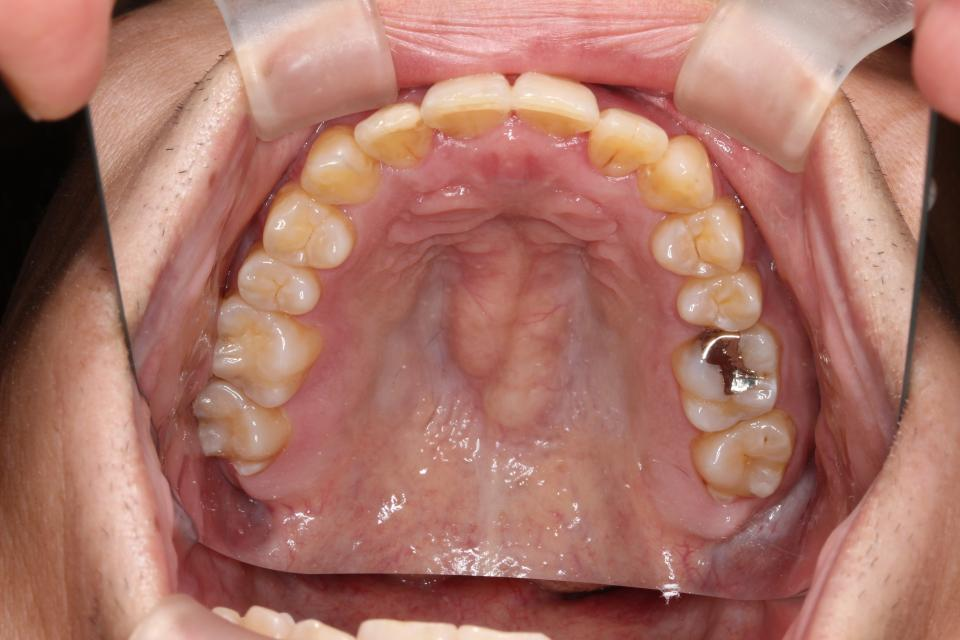

叢生(がたがた)のマウスピース型矯正治療例

矯正治療前

30代男性です。

歯の凸凹が気になると来院されました。

目立たない装置・取り外し可能なマウスピースタイプでの矯正治療を

希望されてましたのでマウスピース型矯正装置(インビザライン)で矯正治療を行いました。

親知らずを3本抜歯して、歯のやすりがけ(IPR)を行っています。